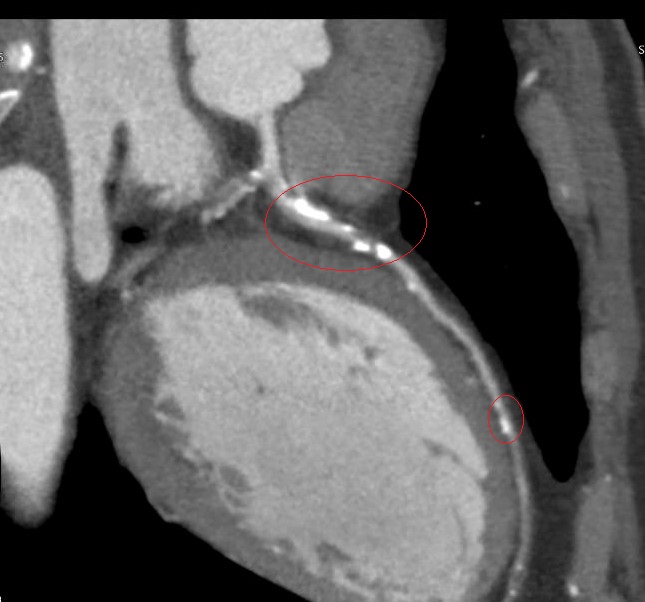

▲「血管內震波碎石術(IVL)」對血管壁更為溫和,能有效降低血管破裂與剝離風險,安全性更高,但目前這項技術尚未納入健保給付。(圖╱彰化醫院提供)

李學林說,醫療團隊透過心導管手術搭配 IVL技術,利用震波氣球貼近血管壁發出超聲壓力波,擊碎血管壁的堅硬鈣化斑塊,讓原本僵硬的血管恢復擴張性,為支架放置創造理想的環境,再植入3支支架,使支架能完整展開、貼合血管,降低支架血栓及再狹窄的風險。

李學林指出,臨床上約有三成冠狀動脈疾病患者伴隨中重度血管鈣化狹窄,鈣化讓血管變硬、難以擴張,造成治療挑戰。相較於傳統治療如切割球囊或鑽石旋磨術,IVL對血管壁更為溫和,能有效降低血管破裂與剝離風險,安全性更高,但目前這項技術尚未納入健保給付。